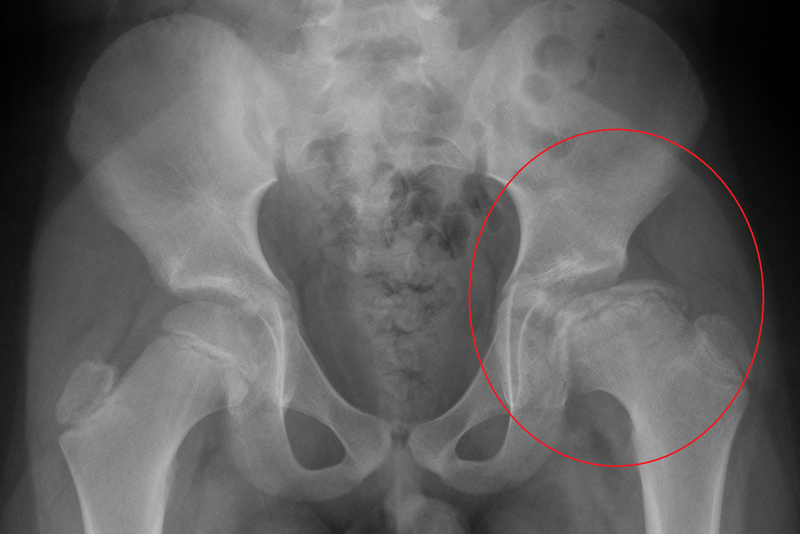

Khi căn bệnh dẹt chỏm xương đùi trở nên rõ ràng về mặt triệu chứng thì bệnh đã vào giai đoạn nặng. Ở trẻ em, do sụn đầu xương có khả năng phát triển nên chiều cao đầu xương bị mất có thể phục hồi được, tuy nhiên ở người lớn sự xẹp xuống là không thể phục hồi được.

Sinh lý bệnh dẹt chỏm xương đùi ở trẻ em và người lớn đều giống nhau. Bệnh được đặc trưng bởi quá trình tự hủy của các tế bào xương - tủy xương và các tế bào hình thành xương - dẫn đến sự sụp đổ của đầu với tổn thương tiếp theo của sụn nằm phía trên, và do đó làm phẳng hình dạng bề mặt tròn của đầu khớp với ổ cối, cuối cùng, gây ra, viêm xương khớp thứ phát.

Thiếu máu có thể phá hủy xương và làm chúng biến dạng vĩnh viễn. Những bóng nằm trên đầu xương đùi và vừa khít với khớp hông, trong tình trạng này, nguồn cung cấp máu cho bóng bị cắt và xương sẽ chết. Phần bị ảnh hưởng của xương đùi trở nên dẹt, biến dạng và có nguy cơ bị bong ra khỏi khớp hông. Lớp sụn hỗ trợ các đầu xương biến mất khiến chúng bị bong ra và gãy.